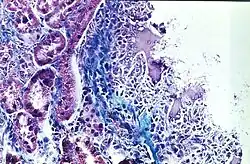

Biocompatibilidad es un término derivado del prefijo bio- (del griego βιοσ, “vida, ser vivo”) y de la palabra compatibilidad (“capacidad de estar con”). Es la capacidad de un material para actuar con una respuesta adecuada del medio biológico en el cual son utilizados (un ser humano u otro ser vivo). Los materiales biocompatibles son llamados biomateriales.

El término biocompatibilidad se aplica principalmente a los materiales médicos en contacto directo, breve o prolongado, con los tejidos y fluidos internos del cuerpo como las sondas, las jeringuillas, las prótesis, etc.

La biocompatibilidad se refiere a la capacidad de un biomaterial para desempeñar la función deseada de acuerdo con el tratamiento médico, sin provocar ningún efecto indeseable local o sistémico en el beneficiario de la terapia, pero al mismo tiempo generando la mejor respuesta celular o del tejido en esa situación específica. Asimismo, puede optimizar el desempeño clínico de dicha terapia (WILLIAMS et al., 2008).